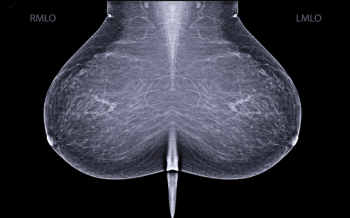

In a large study of nearly 100,000 women, researchers found that the combination of digital breast tomosynthesis (DBT) and synthesized mammography had more than triple the detection rate for invasive breast cancer in extremely dense breasts in comparison to digital mammography alone.

In a retrospective review involving over 2.2 million women with three consecutive biennial mammography screenings and no history of breast cancer, researchers noted that for premenopausal women with fatty breasts at baseline, increasing breast density at subsequent screenings led to significantly elevated hazard ratios ranging from 1.45 to 1.93 for the risk of breast cancer.